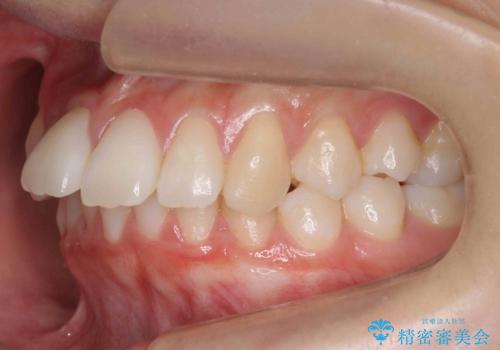

- 前歯が出ていることを主訴に来院。

歯を抜かずにマウスピース矯正をご希望でした。

歯と歯の間をわずかに削り、歯並びを少し横に拡大して並べました。

奥にすき間がなかったため後ろには下げていません。

沢山ひっこめるには4本抜歯でワイヤーの選択肢もありましたが、抜かないでできる範囲をご希望されました。

とがった形の歯列を整えるだけでもだいぶ印象は変わると思います。

今回歯列を広げた結果、上顎犬歯の歯肉は多少退縮しています。